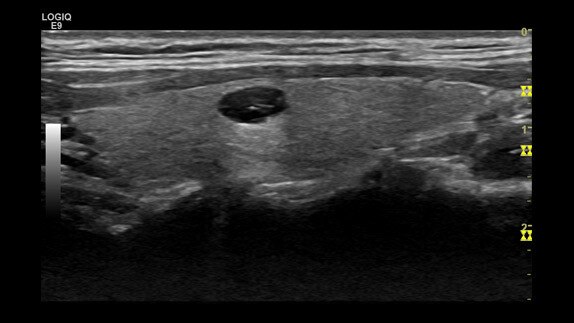

Neurinoma, ML6-15 transducer